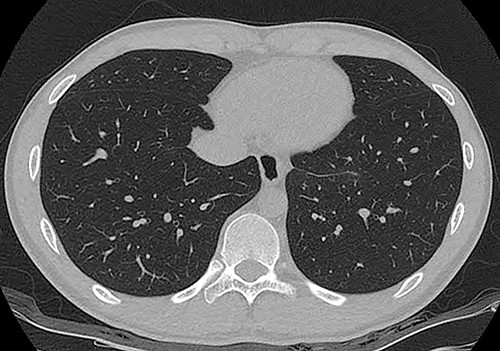

An 18-year-old male patient presented to the emergency department with right-side chest pain of 1-day duration. A plain chest x-ray confirmed a right pneumothorax. A tumor in the left lower paravertebral area was suspected (Fig. 1a). A CT of the chest was performed and showed a 6-cm large, well-defined, probable cystic mass in the left posterior mediastinum, adjacent to the esophagus. Esophageal duplication or bronchogenic or neurenteric cyst was suspected (Fig. 1b and c). The patient was discharged after pneumothorax had improved. Two months later, he was readmitted for surgery to remove the cystic tumor. Single-incision video-assisted thoracoscopic surgery (VATS) was performed to treat the posterior mediastinal tumor. The patient was placed in the prone position. An incision of 4 cm in length was made in the left ninth intercostal space at the lateral line of the scapula. A 5-mm thoracoscope with a 30-degree view was used. A cyst was identified in the posterior mediastinum (Fig. 2a), and a longitudinal incision was made in the mediastinal pleura. The left vagus nerve was placed beside the tumor. The lower half of the cystic mass was embedded in the muscular layer of the esophagus (Fig. 2b) and was in contact with the esophageal mucosa. The cyst was dissected carefully from the surrounding tissue. During dissection, the cyst ruptured, discharging an ivory mucoid creamy fluid. The cyst was completely removed with no injury to the esophageal mucosa. The esophageal mucosa, which was in close contact with the cyst, was stretched and protruding. To cover the exposed esophageal mucosa, the dissected esophageal muscle and periesophageal tissue were approximated with a continuous suture using a barbed suture (V-Loc™ 90, Medtronic) (Fig. 2c). Another barbed suture was used to repair the mediastinal pleura. A 24-Fr chest drain tube was placed through the same port (Fig. 2d). The operation took 80 min. The patient’s diet was started on the evening of the surgery. The chest drain was removed on the 1st postoperative day, and the patient was discharged from the hospital on the 2nd postoperative day without problems. Histopathological examination revealed a bronchogenic cyst. A CT scan of the chest carried out 2 years 7 months after the operation and confirmed that the patient had healed without any complications (Fig. 3).

Radiographs of an 18-year-old man. (a) Simple radiograph shows a tumor in the left lower paravertebral area (arrow head). (b, c) A contrast-enhanced computed tomography scan. A 60 × 36 mm well-defined lobulated cystic mass in the left posterior mediastinum, abutting the esophagus.